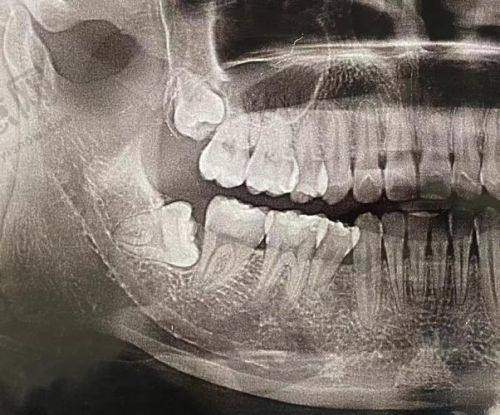

有一位患者牙齿状况较差,存在重度的牙周病,同时伴有牙齿缺失,希望进行种植牙手术。王菁医生先为患者进行了全方面的牙周系统治疗,通过龈下刮治、根面平整等方法改善患者的牙周健康状况。待牙周情况稳定后,为患者制定了穿颧骨种植牙方案。手术过程顺利,术后种植体稳定性良好。在修复期间,王菁医生还对患者进行了种植体的牙周维护,患者的牙齿功能和美观都得到了极大改善,对治疗成效非常满意。